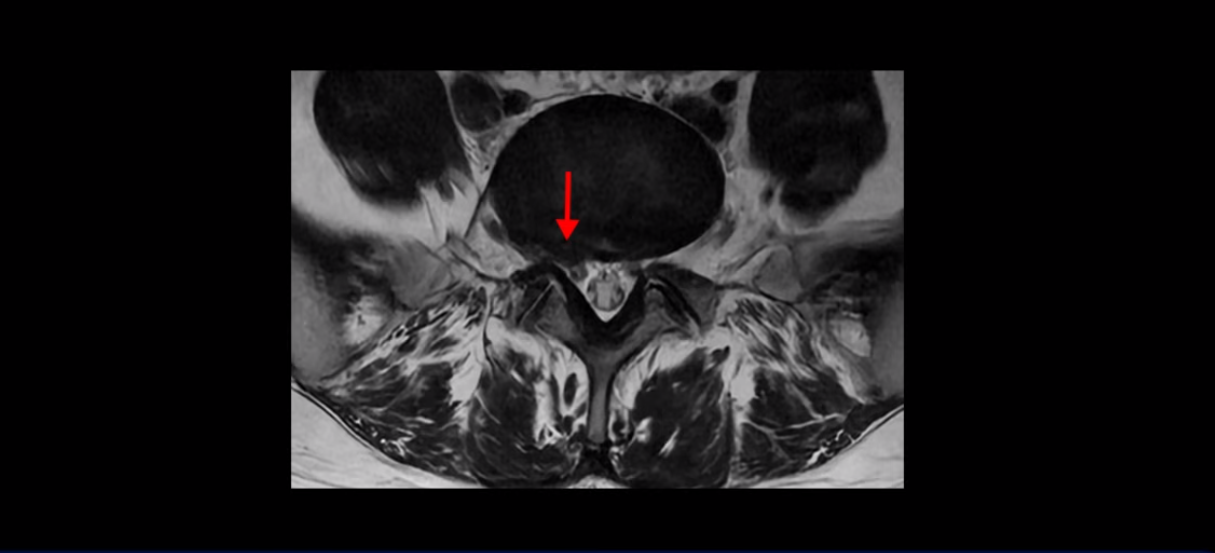

우선 이분 허리 MRI를 보면 5번 1번에 퇴행성 디스크가 있지만 방사통을 일으킬 만큼 신경을 누르고 있어 보이지 않습니다.

4번 5번과 3번 4번 마디도 디스크가 중앙으로 살짝 밀려나와있지만 최근에 섬유륜이 찢어진 것도 아니고, 신경 다발을 누를 정도로 심하게 밀려나와 있는 것도 전혀 아닙니다.

양쪽 신경 가지가 빠져나가는 추간공도 충분히 넓어서 신경학적 방사통을 일으킬 여지가 없습니다.

그럼 이 환자분의 양쪽 다리 저림과 발 저림 그리고 앉기만 하면 5분 내로 심한 허리 통증, 엉덩이 통증이 발생하는 원인은 뭘까요? 저희가 이런 디스크 내장증 얘기를 들으신 환자분들 치료 후기에서 수없이 설명하지만, 이런 증상이 디스크가 원인이 아닙니다. 이분도 여러 병원에서 증상과 MRI가 일치하지 않는다고 들으셨는데요.